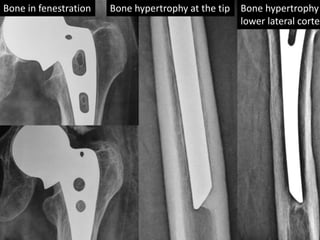

• All AMP were done in young age lasted long.

• Good quality bone support AMP well.

• Bone growth is noted in fenestrations of AMP.

• Hypertrophy of the calcar region noted in all

cases.

• There was no sign of loosening in any case.

• There was no sinking of proximal prosthesis in

femoral canal.

Bone in fenestration Bone hypertrophy at the tip Bone hypertrophy

lower lateral cortex

Bone in fenestrationBone hypertrophy at the tip Bone hypertrophy lower lateral cortex